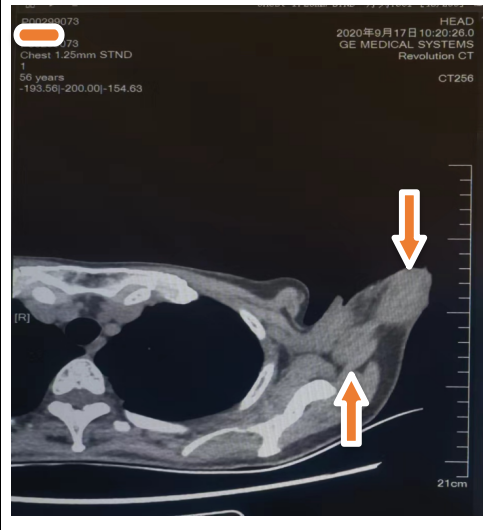

治疗2个月后 2020年9月17日